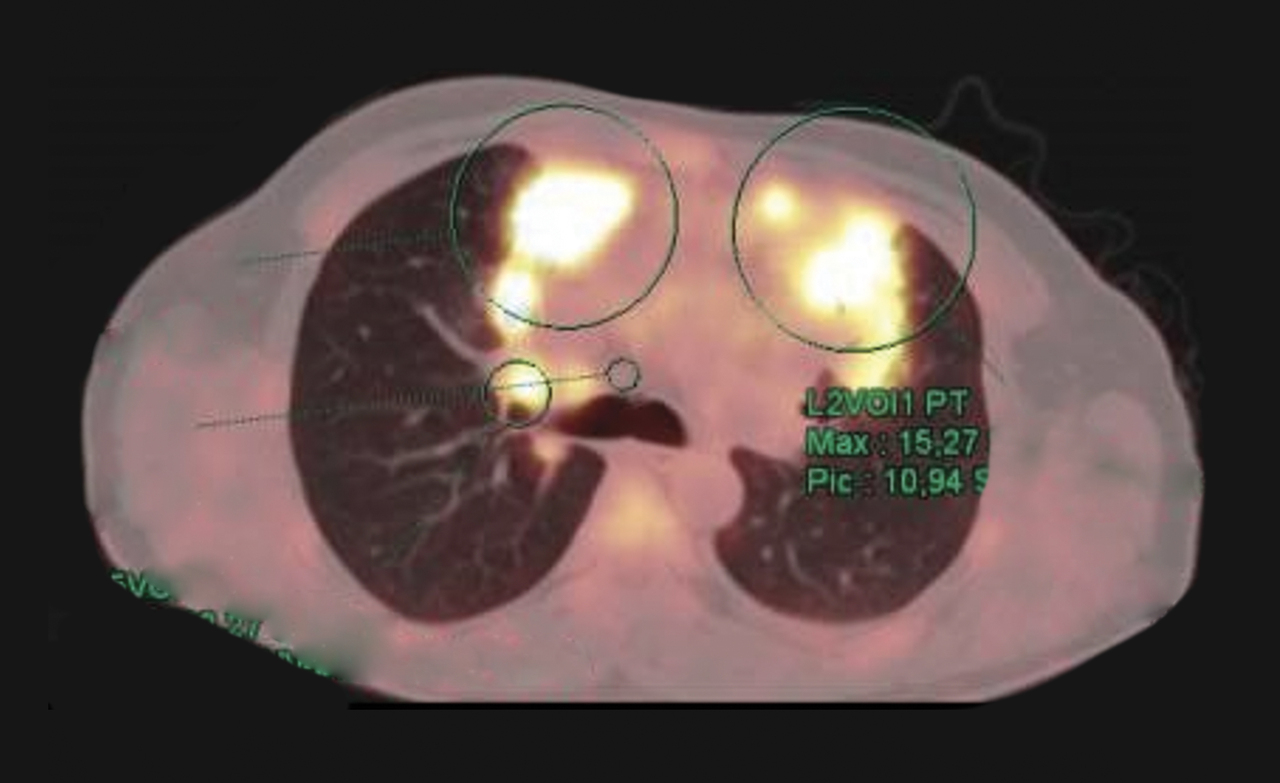

Homme de 39 ans ayant des douleurs thoraciques, une altération de l’état général et une masse médiastinale découverte sur la tomodensitométrie.